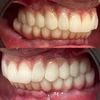

%100 hasta memnuniyeti odaklı çalışan ve her bir hasta için özel tedavi planlaması prensibi ile hastalarının yaşamına dokunan Dt. Bende Doğan, bu zamana kadar binlerce smile design, implant, restorasyon ve kanal tedavisi uygulamasına imza atarken, hasta referansıyla çalışma disiplini ile faaliyet göstermektedir.

Zirkonyum uygulamalar

Porselen uygulamaları

Laminate veneer